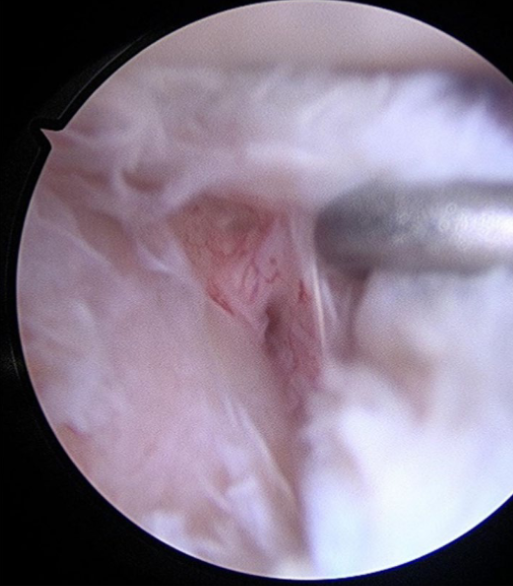

Arthroscopic Single-Layer Hyaluronate-Based Scaffold for Osteochondritis Dissecans of the Glenoid – Copy

Alessandro Donà M.D. | Rocco Bonfatti M.D. | Chiara Manzini M.D. | Elisa De Santis Ph.D. | Gian Mario Micheloni M.D. | Andrea Giorgini M.D.